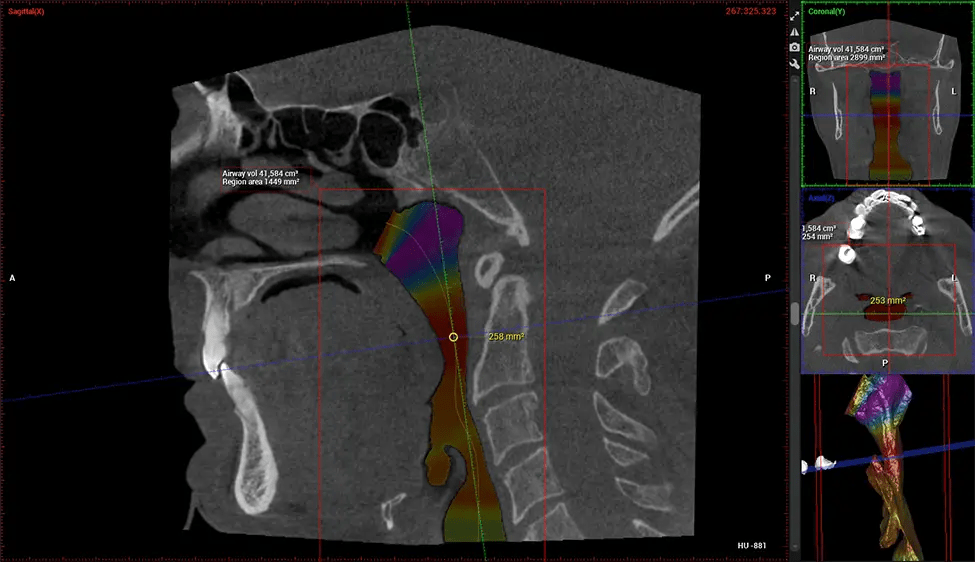

Después del proceso de escaneo, las imágenes de rayos X capturadas son procesadas por el software CBCT, que aplica algoritmos para reconstruir una imagen 3D detallada del área escaneada. El software recopila estas imágenes de rayos X individuales y crea una representación digital en 3D de la anatomía del paciente. El dentista o el radiólogo pueden ver y analizar la imagen CBCT 3D reconstruida. Esta imagen se puede manipular, rotar y acercar o alejar para examinar estructuras específicas y evaluar la condición del paciente.

Planmeca Viso G7 CBCT (Cone Beam CT Scan) está diseñado para superar las demandas de los líderes de la industria, los especialistas y las grandes instituciones. Tiene un gran sensor de ø25×30 cm con cuatro cámaras integradas. Puede capturar tamaños de volumen ilimitados, desde ø3×3 cm hasta ø30x30cm, capturando el casquete escutelario a través de C7 en la columna cervical. Planmeca Viso G7 ofrece el escaneo de volumen único más grande de la industria de ø30×19 cm. Está preparado para manejar modalidades de imágenes avanzadas como la tecnología Planmeca ProFace® y Planmeca 4D™ Jaw Motion. El soporte occipital para la cabeza permite una visión sin obstáculos del tejido facial.